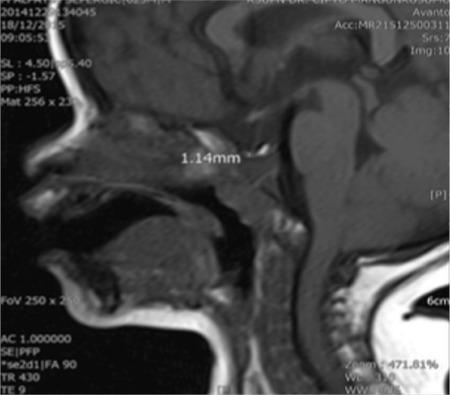

Isolated growth hormone (GH) deficiency (IGHD) type 2 is a rare autosomal dominant disorder characterized by severe short stature with low GH level. Timely diagnosis is important for optimal results of recombinant human GH (rhGH) treatment and detection of additional pituitary deficiencies in affected relatives. A male child presented at the age of one year with severe, proportionate short stature [-4.9 standard deviation score (SDS)] and with a normal body mass index (-1.1 SDS). Physical examination revealed frontal bossing, midfacial hypoplasia, normal external genitalia and no dysmorphic features. Paternal and maternal heights were -6.1 and -1.9 SDS. Serum insulin-like growth factor-1 (IGF-1) and IGF-binding protein-3 were undetectable and the peak GH concentration by clonidine stimulation test was extremely low (0.18 ng/mL). Brain magnetic resonance imaging showed anterior pituitary hypoplasia. Genetic analysis identified a novel heterozygous mutation (c.291+2T>G) expected to lead to splicing out exon 3 of GH1. rhGH from age 2.4 years led to appropriate catch-up. In conclusion, we identified a novel gene mutation in an infant with classical IGHD type 2 presentation.

2型孤立性生长激素(GH)缺乏症(IGHD)是一种罕见的常染色体显性疾病,其特征为严重身材矮小且GH水平低。及时诊断对于重组人生长激素(rhGH)治疗的最佳效果以及检测受影响亲属的其他垂体功能缺陷非常重要。一名男童在1岁时就诊,有严重的匀称性身材矮小[-4.9标准差评分(SDS)],体重指数正常(-1.1 SDS)。体格检查发现前额突出、面中部发育不全、外生殖器正常且无畸形特征。其父亲和母亲的身高分别为-6.1 SDS和-1.9 SDS。血清胰岛素样生长因子-1(IGF-1)和IGF结合蛋白-3检测不到,可乐定刺激试验的GH峰值浓度极低(0.18 ng/mL)。脑部磁共振成像显示垂体前叶发育不全。基因分析确定了一个新的杂合突变(c.291+2T>G),预计该突变会导致GH1基因的第3外显子被剪接掉。从2.4岁开始使用rhGH治疗后实现了适当的追赶生长。总之,我们在一名具有典型2型IGHD表现的婴儿中鉴定出了一种新的基因突变。